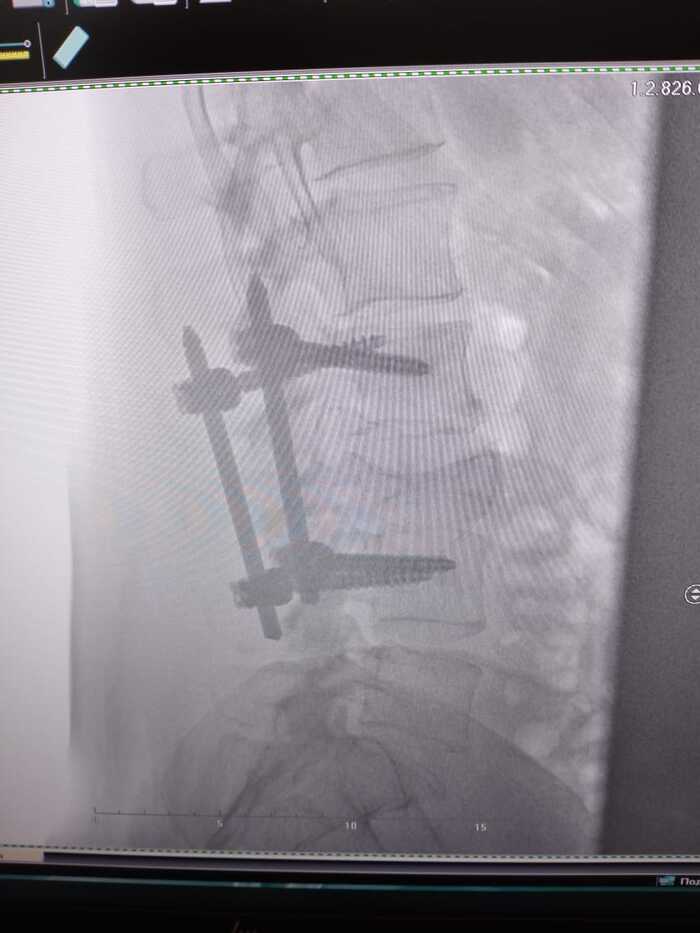

В течении года продолжалось восстановление- таблеточки, витаминчики. Из улучшений- меньше стала болеть нога, отросли волосы, прошли побочки химии. Со спиной все по разному, боли то есть то нет и появилась грыжа Шморля- как сказал ортопед , она появилась из за того что конструкция ослабла и болт один просел и царапает позвонок и из за этого боли и грыжа ( но болт поцарапает до определённого момента и перестанет , и боли пройдут). Еще сказал что можно или удалить всю эту конструкцию или распространить на позвоночник дальше, но это по рекомендации онкологов- нужно ехать в Москву и там консультироваться с онко и ортопедами( а это лишние деньги, возможно после нового года поеду). В конце ноября был куплен велотренажёр, и спустя пару недель занятий больная нога стала работать лучше, смог отталкиваться - очень большой плюс. Из минусов ещё появились проблемы со зрением, выявили астигматизм и прописали очки но носить не могу так как начинает тошнить..

В понедельник был на кт, изменений никаких нет по онкологии - все так же стабилизация, только нашли грыжу Шморля.